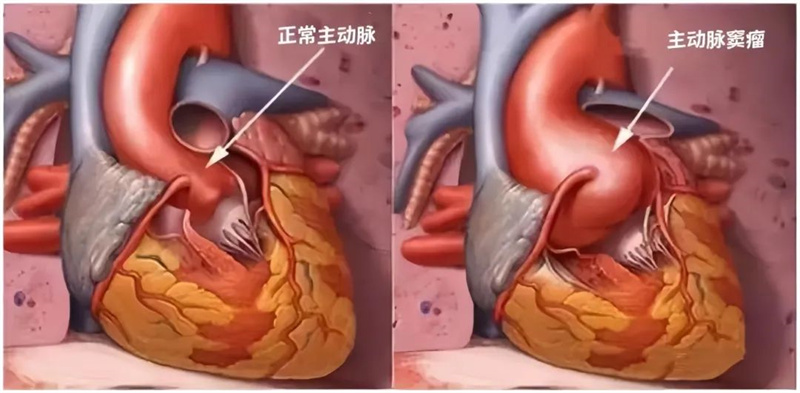

入院心脏彩超显示:小刘主动脉窦部扩张,直径约52mm,升主动脉扩张,直径约43mm,升主动脉壁菲薄如纸,右冠状窦瘤形成且大部分瘤体已脱入室缺,这意味着如不及时治疗,小刘心脏里的“定时炸弹”将随时引爆,而他却不自知。

考虑到患者病情的复杂性和年龄较轻,心外科李保军主任带领团队经过慎密分析讨论,为使患者获得最佳的手术治疗效果而制定了最优的治疗方案——采用目前较新颖且较复杂的“Florida sleeve”套管技术行主动脉根部修复术,代替根部置换术,保留自身瓣膜。

李保军主任提到, “Florida Sleeve”根部重塑技术是一项复杂的心外科手术,在保留主动脉瓣的同时缩小了主动脉瓣环和主动脉根部,避免了主动脉根部置换人工机械瓣膜后相关血栓和出血的风险,也避免了置换人工生物瓣膜后,未来生物瓣膜衰败可能需要再次手术的麻烦。特别是针对主动脉根部瘤或主动脉夹层但主动脉瓣正常的患者,应用该技术能够取得更好的手术远期效果。